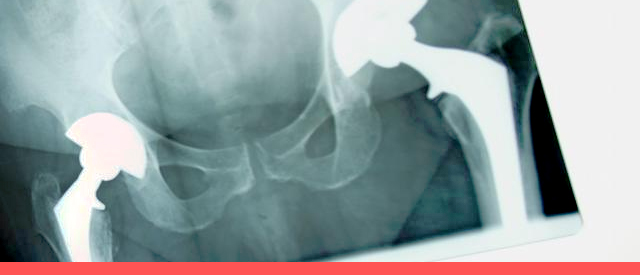

晚期患者关节强直,除了脊柱活动度消失,无法活动颈部、弯腰、扭腰以外,最严重的问题就是髋关节强直。关节一旦出现强直,药物治疗手段将回天无力,只有通过外科介入才能改善。外科治疗的时机是:内科治疗无效,合并关节功能障碍或畸形,日常生活受到影响。

近年来,人工全髋关节置换术的出现,为合并髋关节强直的患者带来了福音。人工关节置换术可切除骨性融合的股骨头和髋臼,转而在原髋臼的位置重新置入人工髋臼,同时,在股骨上段重新置入股骨柄和股骨头人工关节假体,从而再造髋关节,恢复髋关节的活动功能。通过人工全髋关节置换,可以重新赋予患者正常的行走功能,给晚期的强直性脊柱炎患者创造崭新的生活。